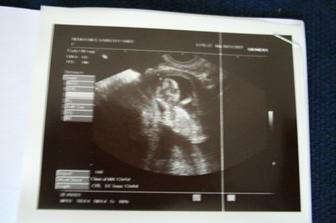

Ve 26tt 3D ultrazvuk - miminko natočeno na dvd 🙂.

15.4.2010 kontrola u dr. Utz ve 32. týdnu. Miminko přetočené hlavičkou dolů, váha 1589g, srdíčko bije jako zvon.